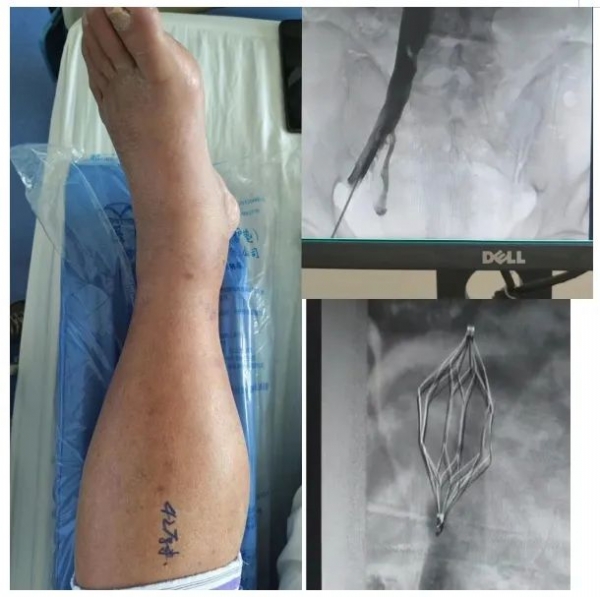

下肢静脉血栓滤器是一种介入性治疗器械,其设计原理基于捕捉和拦截从下肢脱落的大块血栓,防止其进入肺动脉造成致命的肺栓塞。滤器通常通过血管介入技术植入下腔静脉,具有操作简便、创伤小、恢复快等特点。滤器的使用可以显著降低肺栓塞的发生率,为下肢静脉血栓的治疗提供了有力的保障。在临床实践中,下肢静脉滤器置入的应用范围广泛。对于急性下肢深静脉血栓患者,尤其是存在抗凝禁忌或抗凝治疗失败的患者,滤器治疗成为了一种重要的治疗选择。此外,对于因手术、创伤或长期卧床等原因导致的下肢静脉血栓患者,滤器治疗同样具有显著的治疗效果。然而,尽管下肢静脉血栓滤器治疗具有诸多优势,但在实际应用中仍需注意一些问题。首先,滤器的植入需要在专业医生的指导下进行,确保操作规范和安全。其次,患者需要定期进行复查和随访,以便及时发现并处理可能出现的并发症。此外,滤器的长期植入可能会对血管造成一定的刺激和损伤,因此,在滤器植入后,患者需严格遵医嘱进行抗凝治疗,以降低血管损伤的风险。随着医疗技术的不断进步,下肢静脉血栓滤器治疗也在不断创新和完善。目前,市场上已经出现了多种类型的滤器,如可回收滤器、临时滤器等,以满足不同患者的治疗需求。同时,随着影像技术的发展,滤器的植入和取出过程也变得更加精确和安全。未来,下肢静脉血栓滤器治疗有望在更多领域得到应用。例如,在预防恶性肿瘤患者因手术或化疗导致的下肢静脉血栓方面,滤器治疗将发挥更大的作用。此外,随着材料科学的进步,新型滤器的研发也将为治疗下肢静脉血栓提供更多选择。总之,下肢静脉血栓滤器治疗作为一种新型的介入性治疗手段,以其独特的优势在临床实践中得到了广泛应用。作为“血管的安全壁垒”,它有效地降低了肺栓塞的风险,提高了患者的生活质量。随着技术的不断进步和创新,相信下肢静脉血栓滤器治疗将在未来发挥更大的作用,为更多患者带来福音。